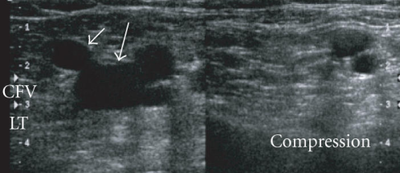

Normal

- Each segment of vein identified must be assess as compressible and noncompressible

- Touching of the anterior and posterior walls indicates a normal exam

- No touching with pressures sufficient to deform the artery indicates DVT